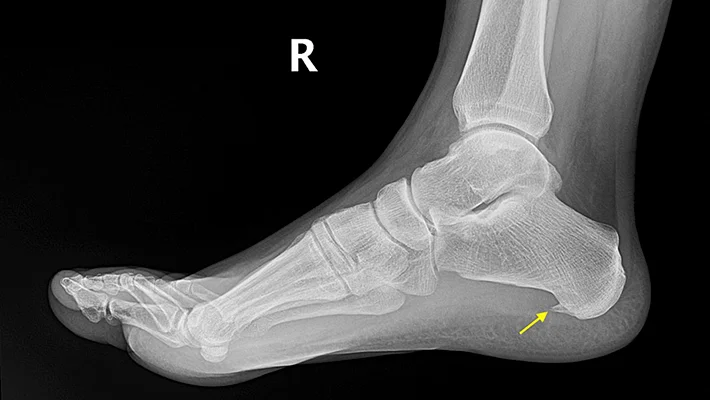

- Рентген. На снимках при таком диагнозе будет заметно шиповидное образование на пяточной кости.